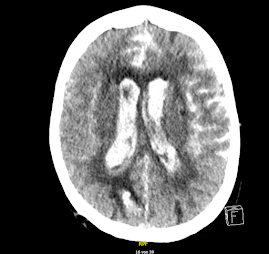

"Vidíme rozsáhlé subarachnoidální krvácení s provalením do mozkových komor", shrnuje profesor radiologie to, je nepřehlédnutelné. "Zdrojem tohoto krvácení je velké aneurysma při rozdvojení bazilární tepny." Pak se objeví další obrázek, starší. "Tady je CT - obrázek z roku 2018. To aneurysma je tam vidět ve stejném rozsahu."

Ano, v roce 2018 měla paní lehkou cévní příhodu. Mrtvici a byla kompletně vyšetřena. Včetně CT-angiografie, zobrazení cév, které tuhle výduť odhalilo.

O tom aneurysmatu se vědělo od roku 2018. Byl to tenkrát náhodný nález, nemocná s ním neměla potíže. Zajímalo by tedy i mne, proč byla taková věc ignorována. Intervence byly už v té době na vysoké úrovni. Samozřejmě aneurysma v takovém místě není jednoduché ošetřit a hrozí komplikace. Například, že se při výkonu ztrombotizuje a uzavře některá z hlavních tepen. Pokud by se to stalo právě na bazilární tepně, nemocná by to nejspíš nepřežila a pokud ano, tak jako vrak. Že by strach z komplikace vedl k tomu, že se nález raději nechal na pokoji? Nechtěla sama nemocná na operaci? Nebo tak rozhodli příbuzní? Tím ji sice odsoudili, že bude mít v hlavě časovanou bombu. Nebo jí taky darovali 4 roky života, kdo ví?